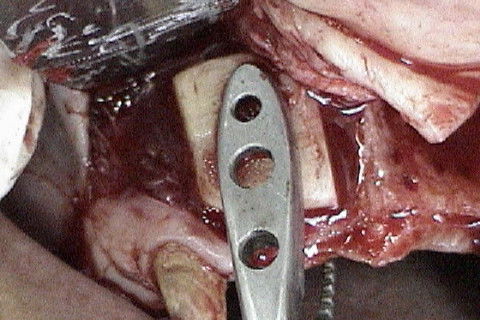

Bloco ósseo sendo fixado com o auxilio de pinça porta-enxerto